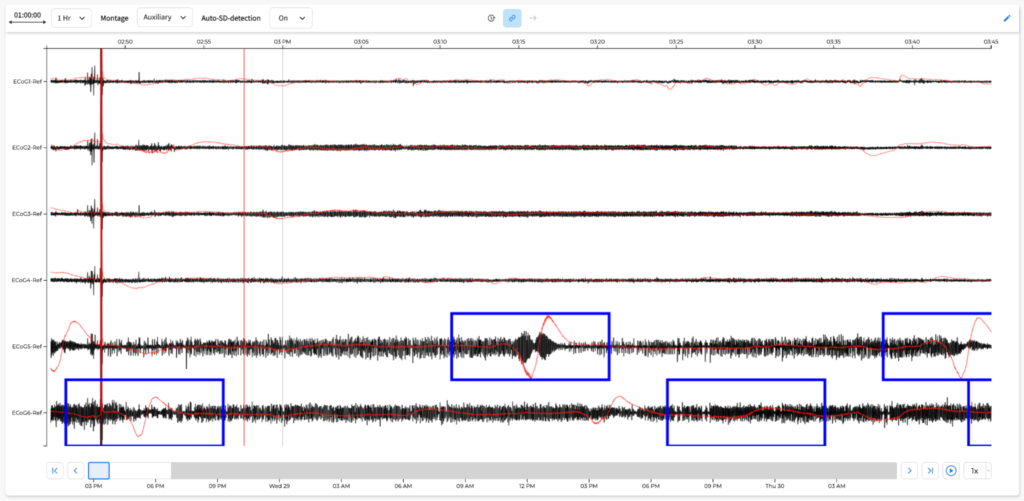

Some apps are being developed internally by our team and others are being developed by our partners. We’ve developed a software development kit that outlines what is needed for third-party integration. Our pilot clinical sites will have access to these apps as they become available for beta testing. This feedback will be instrumental as our app store matures. For instance, we have integrated Dr. Jed Hartings’ cortical spreading depolarization detection algorithm for real-time use (OpenSD), and the University of Cincinnati Medical Center neuro ICU will be one of the first testing sites. This is just one example of over 20 apps that we are planning to release over the next year: